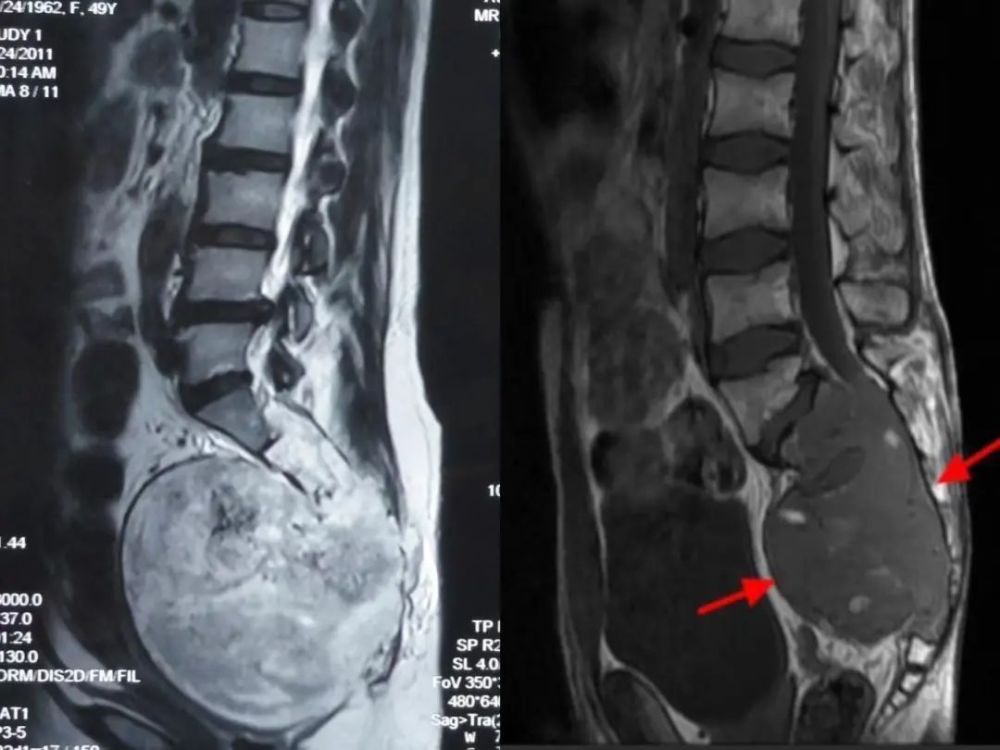

影像学显示存在占位和骨破坏,不像“好东西”。丨作者供图

作者术前高度怀疑的脊索瘤是一种会发生于颅底和脊柱的罕见肿瘤,属于骨与软组织恶性肿瘤。约50%的脊索瘤发生于脊柱末端,即骶骨(如下图)。

巨大骶骨脊索瘤典型影像学表现丨医生供图